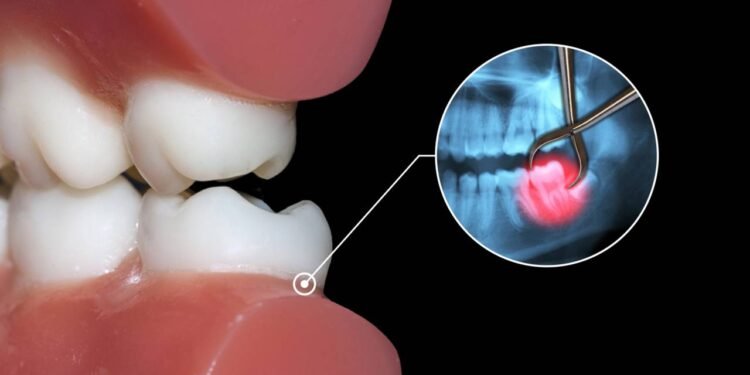

A extração do dente do siso costuma ser indicada quando o terceiro molar causa dano ou oferece risco concreto aos demais dentes e estruturas da boca. Um exemplo frequente é o siso que nasce inclinado, empurrando o dente vizinho, acumulando placa bacteriana e facilitando inflamações recorrentes na gengiva, quadro conhecido como pericoronarite.

Outro motivo comum para remover o siso é a dificuldade de higienização, sobretudo quando o dente está parcialmente coberto pela gengiva ou muito distante do alcance da escova. Em situações mais complexas, o exame de imagem pode revelar siso incluso, cistos associados à coroa do dente ou sinais de reabsorção da raiz do molar vizinho, indicando a necessidade de uma remoção planejada.